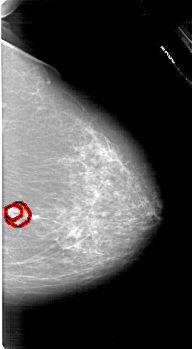

A_1618_1.RIGHT_MLO

RIGHT_MLO LINES 6301 PIXELS_PER_LINE 3661 BITS_PER_PIXEL 12 RESOLUTION 43.5 OVERLAY

FILE: A_1618_1.RIGHT_MLO.OVERLAY

TOTAL_ABNORMALITIES 1

ABNORMALITY 1

LESION_TYPE MASS SHAPE IRREGULAR MARGINS SPICULATED

ASSESSMENT 5

SUBTLETY 3

PATHOLOGY MALIGNANT

TOTAL_OUTLINES 2